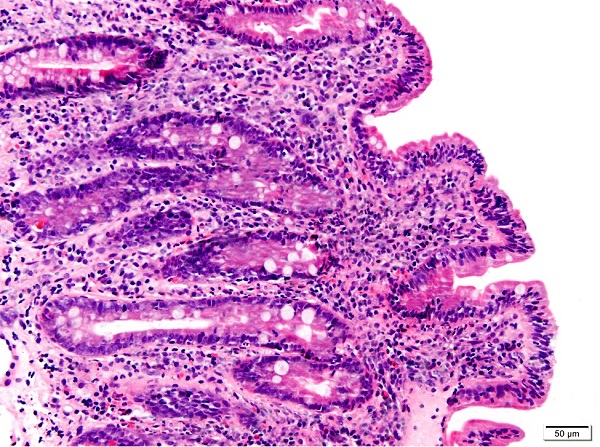

Se detecta la existencia de anticuerpos antitransglutaminasa diez veces por encima del límite alto de la normalidad (niveles de 629,00 IU, resultado positivo >10). Se completa estudio con endoscopia digestiva alta. La biopsia duodenal muestra atrofia vellositaria moderada con linfocitosis intraepitelial difusa e hiperplasia de criptas glandulares, sin evidencia de G. intestinalis, compatible con enfermedad celíaca 3b de Marsh modificado (Fig. 3). Con el diagnóstico de enfermedad celíaca, se inicia dieta exenta de gluten y sulfato ferroso oral. De forma evolutiva, se constata la progresiva negativización de los anticuerpos, así como la desaparición del trastorno de la conducta alimentaria.

| Figura 3. Corte histológico de duodeno teñido con hematoxilina-eosina. Se evidencia la tríada atrofia vellositaria moderada, hiperplasia críptica y linfocitosis intraepitelial |